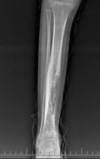

Cisto ósseo simples com fratura

Lesão litica unicameral.

Localização: úmero proximal e femur (< 20 anos) ou calcâneo, talus, ileo (> 20 anos).

Se fratura: Sinal do fragmento caído.